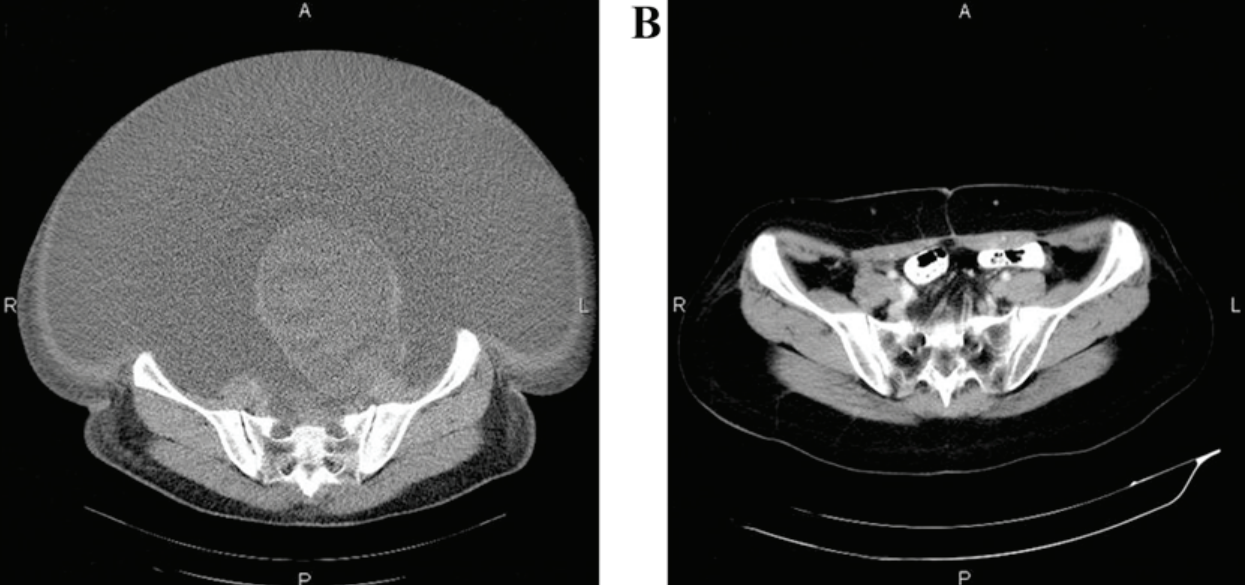

近日,《Neuro-Oncology》在线全文发表了埃克替尼联合阿美替尼一线治疗EGFR突变伴脑转移非小细胞肺癌患者的疗效与安全性的一项I/II期临床研究的研究结果。